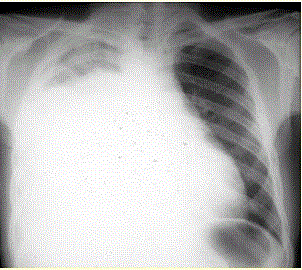

问题  患者男,34岁。进行性胸闷、气促1个月余,伴有干咳、右胸隐痛以及消瘦,无咯血、发热、盗汗、潮热等。 该患者的初步诊断是(提示 胸部X线检查如图所示。)

选项 A、肺血栓栓塞症 B、右侧气胸 C、右侧液气胸 D、右侧大叶性肺炎 E、右侧气胸 F、右侧肺不张 G、右侧大量胸腔积液

答案 G